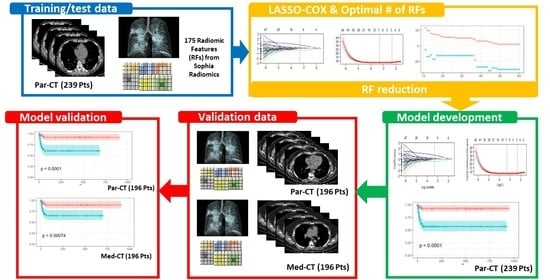

2.3. Predictive Model Building

2.3.1. Feature Selection

2.3.2. Bayesian Information Criterion (BIC)

2.3.4. Model Evaluation through Survival Curves

3.3. LASSO-Cox for Feature Selection